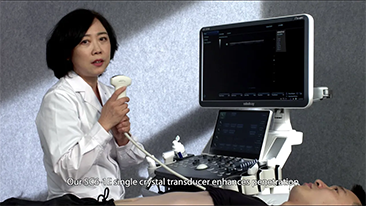

Zorg met minder stethoscoop, meer echografie?

Geoptimaliseerde workflows in gynaecologie en verloskunde zijn noodzakelijk ter ondersteuning van grote pati?ntenvolumes aan screeningbezoeken voor vrouwen. Misvormingen van het centrale zenuwstelsel (CZS) zijn bijvoorbeeld een van de meest voorkomende aangeboren afwijkingen. Als gevolg van verschillende beeldvormingscondities, zoals een slechte foetale positie, is de MSP zeer moeilijk te vinden in een 2D-echografie. Daarom kunnen geautomatiseerde detectie en metingen de scaneffici?ntie sterk verbeteren.